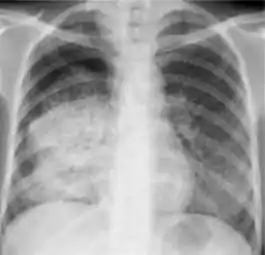

Chest x-ray showing patchy opacification on the upper right and mid-zone lung with fibrotic shadows, as well as bilateral hilar lymphadenopathy.

Chest x-ray showing coarse reticulonodular densities on the lower right lung of post-primary pulmonary TB.